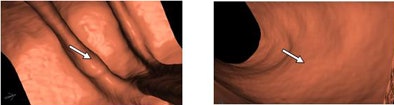

| True-positive results were typically raised lesions characterized by granular or carpetlike morphology. |

![]() |

| False-negative results tended to be flatter lesions, or those located on haustral folds. |

The system's successful detection of slightly raised submucosal lesions "should hardly come as a surprise based on the way we do candidate generation," Slabaugh said. "Raised lesions were characterized by granular or carpetlike morphology, while [CAD] false negatives tended to be flatter."

Other false negatives were subtle lesions located on haustral folds, he said.